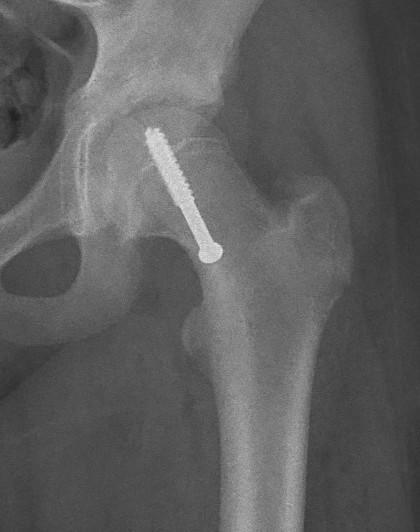

Intra-capsular / Subcapital

Types

Dunn

- trapezoid osteotomy

Fish

- cuneiform